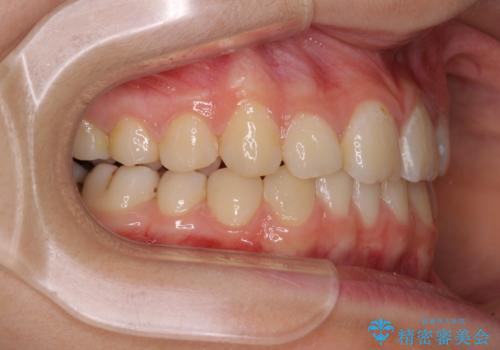

まずは補助装置を用いて八重歯を改善し、インビザラインにて歯列を整えましたが、当初の懸念が的中し、臼歯部の咬合を安定させることができませんでした。

海外留学の予定もあったため、後半は上下ワイヤー装置にて矯正治療を継続し、違和感なく咬合させることとなりました。